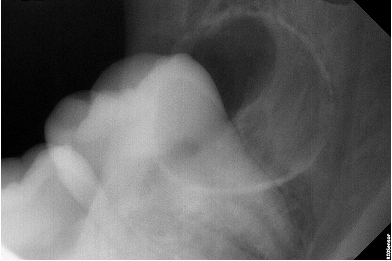

Опыт работы более 3 лет. Внимательный, вежливый доктор, специализируется на хирургической стоматологии. Лечит различные патологии челюсти: кисты, воспалительное заболевания ЧЛХ, удаляет сложные ретинированные зубы мудрости. Осуществляет дентальную имплантации, используя различные методики восстановления костной ткани.